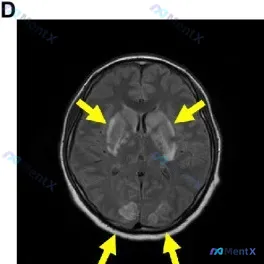

看到一份很有警示意义的头颅MRI FLAIR影像,整理一下思路,避免大家踩临床思维的坑。 --- 先看影像核心发现 - 部位与分布:双侧基底节区(尾状核头部、壳核)+ 双侧枕叶皮层/皮层下,高度对称性的斑片状FLAIR高信号 - 其他细节:脑室形态正常,中线居中,没有明显占位效应,脑沟也没有明显因水...